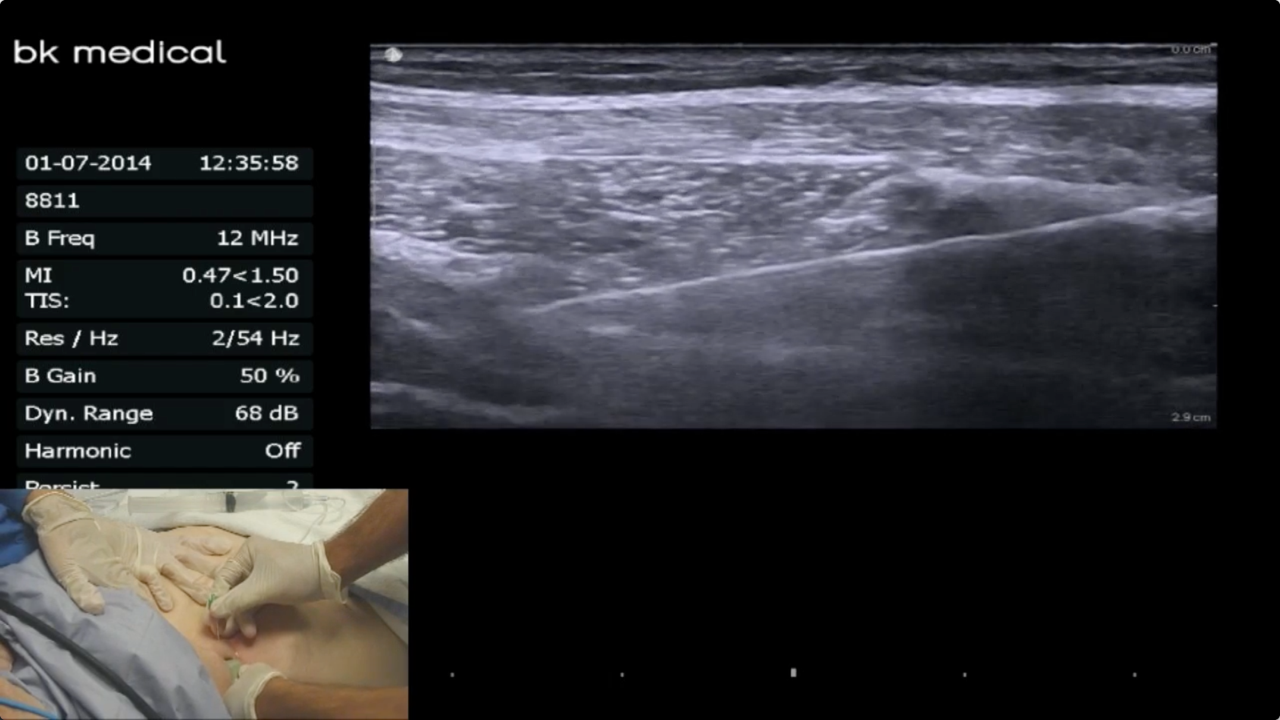

• Ultrasound Guided Posterior TAP Block

Brandon Winchester demonstrates a unilateral ultrasound-guided posterior TAP block for a right inguinal hernia repair.